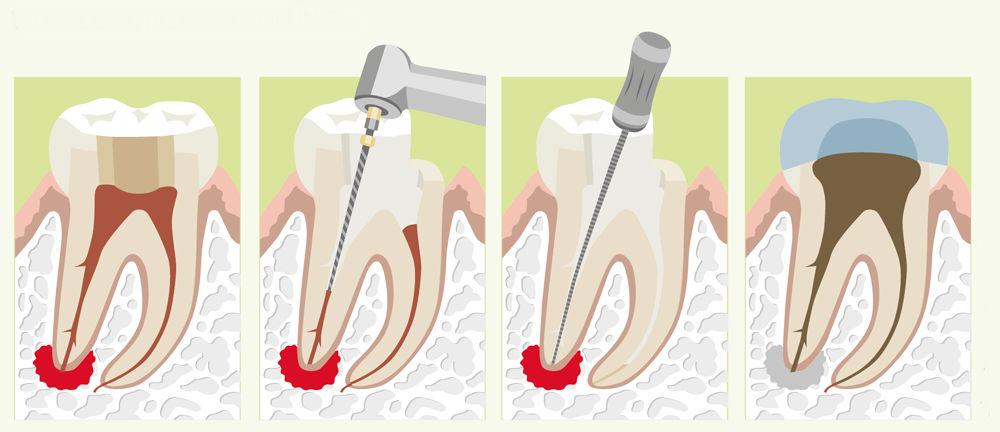

Реплантация зуба: Этапы и особенности операции